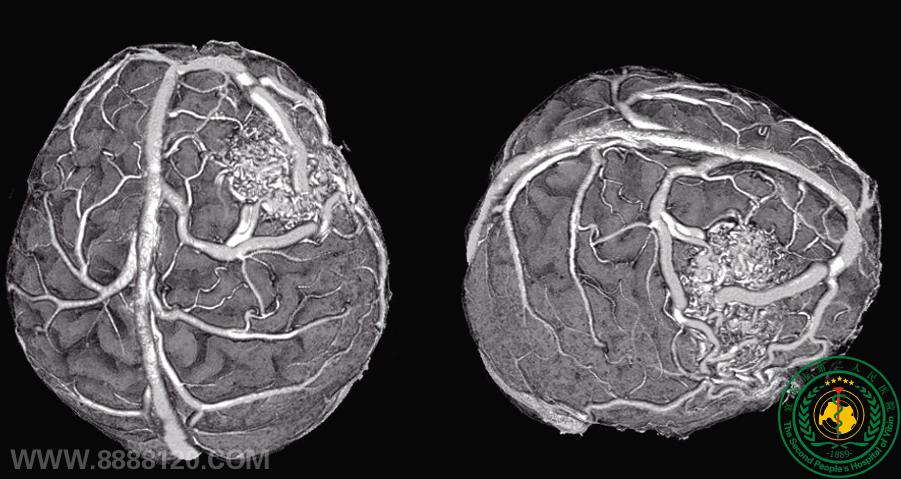

清晰显示颅内动脉瘤           显示颅内肿瘤与血管之间的关系